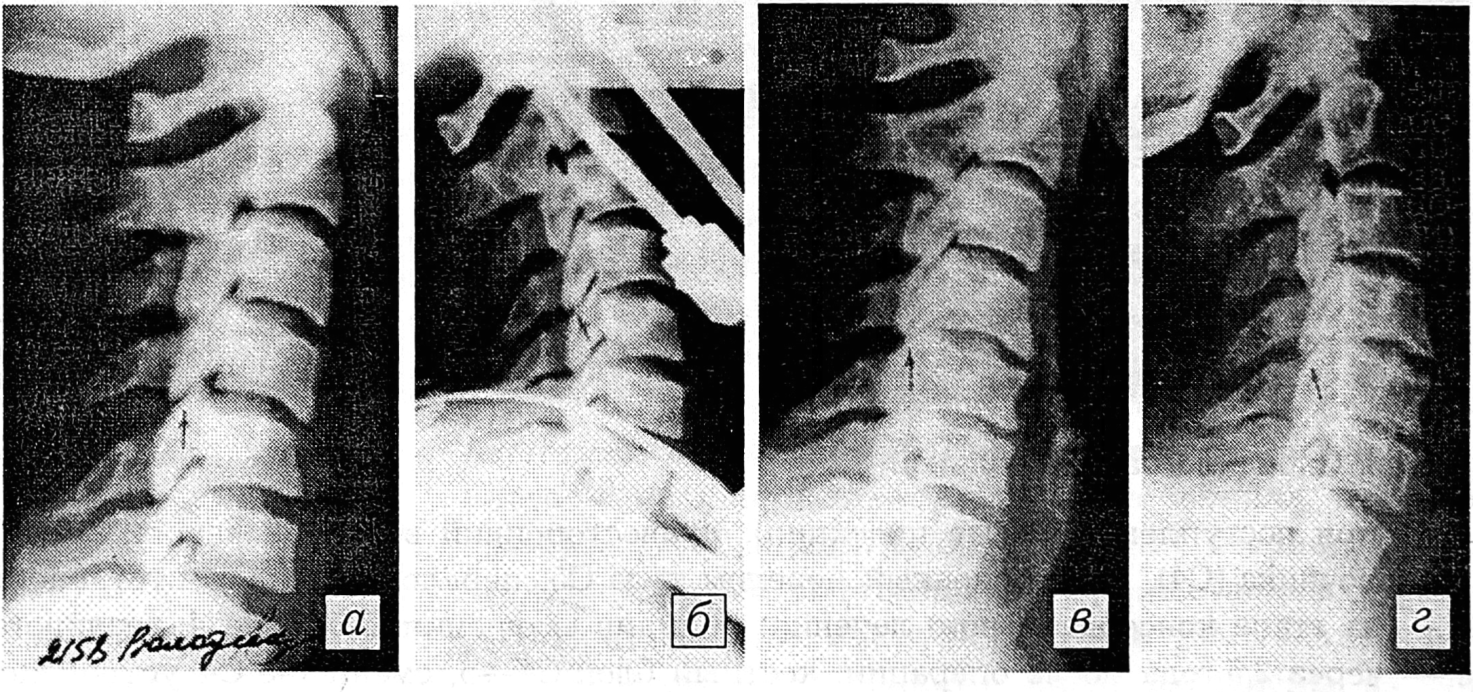

На рентгенограммах определяются снижение высоты тела С5 позвонка в переднем отделе, деформация позвоночника на уровне С4—5 с углом, открытым кпереди, смещение тела позвонка С4 кпереди на 1,5 мм и смещение в дугоотростчатых суставах на 1/2 суставных поверхностей (рис. 2, а). Диагностированы двусторонний опрокидывающийся подвывих в шейном отделе позвоночника (двигательный сегмент С4—5), компрессионный перелом тела С5, абсолютная костно-диско-связочная нестабильность благоприятная (АДСН-II).

Произведена закрытая репозиция нашим устройством с узлом дозированного вправления (рис. 2, б). Штанги головодержателя закреплены в достигнутом положении, узел дозированного вправления демонтирован. Через 5 нед демонтировано все устройство. В дальнейшем иммобилизация осуществлялась торакокраниальной гипсовой повязкой (до 4 мес с момента травмы). На контрольных функциональных рентгенограммах патологической подвижности двигательного сегмента С4—5 не выявлено. Спустя 3 мес больной приступил к прежней работе (шофер). Осмотрен через 8 лет: жалоб не предъявляет, признаков нестабильности нет (рис. 2, в, г).

Рис. 2. Спондилограммы больного В.

а — при поступлении: двусторонний опрокидывающийся подвывих в шейном отделе позвоночника (С4), компрессионный перелом тела С5 позвонка I степени, АДСН-II; б — этап репозиции: восстановлено соотношение в дугоотростчатых суставах (С4—5); в, г — через 8 лет после травмы (в — сгибание, г — разгибание): нестабильности нет, признаки остеохондроза.